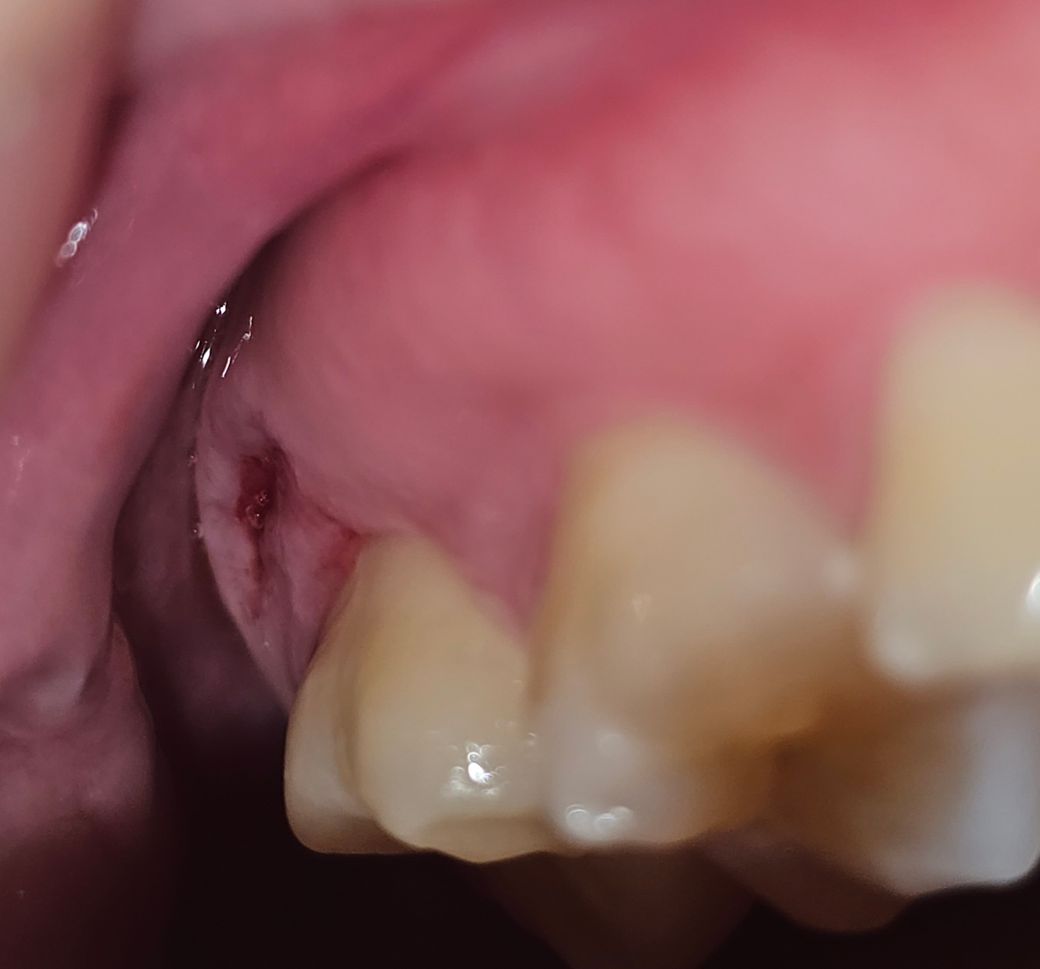

며칠전부터 위에 바깥쪽 뒤에있는 잇몸쪽이 점점 움푹 들어가서 손으로 좀 건드렸더니 피도납니다. 파인부분에 뼈같은 딱딱한 것도 느껴지는데 사랑니가 나오는중인건가요? 근데 이 위치에 나오는게 맞는지 싶고.. 밑에는 통증부위 사진입니다

잇몸이 안으로 푹 들어간 이유를 찾아야 될 것으로 생각됩니다. 사랑니가 나올 부위는 아닌 것으로 보이며 음식을 먹다가 해당 부위에 자극이 되었거나 손상을 받았을 가능성이 높습니다.

파인 부위에서 딱딱한 느낌이 나는 경우 사랑니가 나오고 있는 것일 가능성이 높으며, 사랑니가 나오는 과정에서 잇몸에 압력이 가해져 잇몸이 파이거나 붓는 경우가 종종 있습니다.

농양이 잡혀 피고름이 나오고 있는 것이 아닐까 의심되며 치과에 가서 검사를 통해 원인 치아나 잇몸을 찾아봐야 합니다